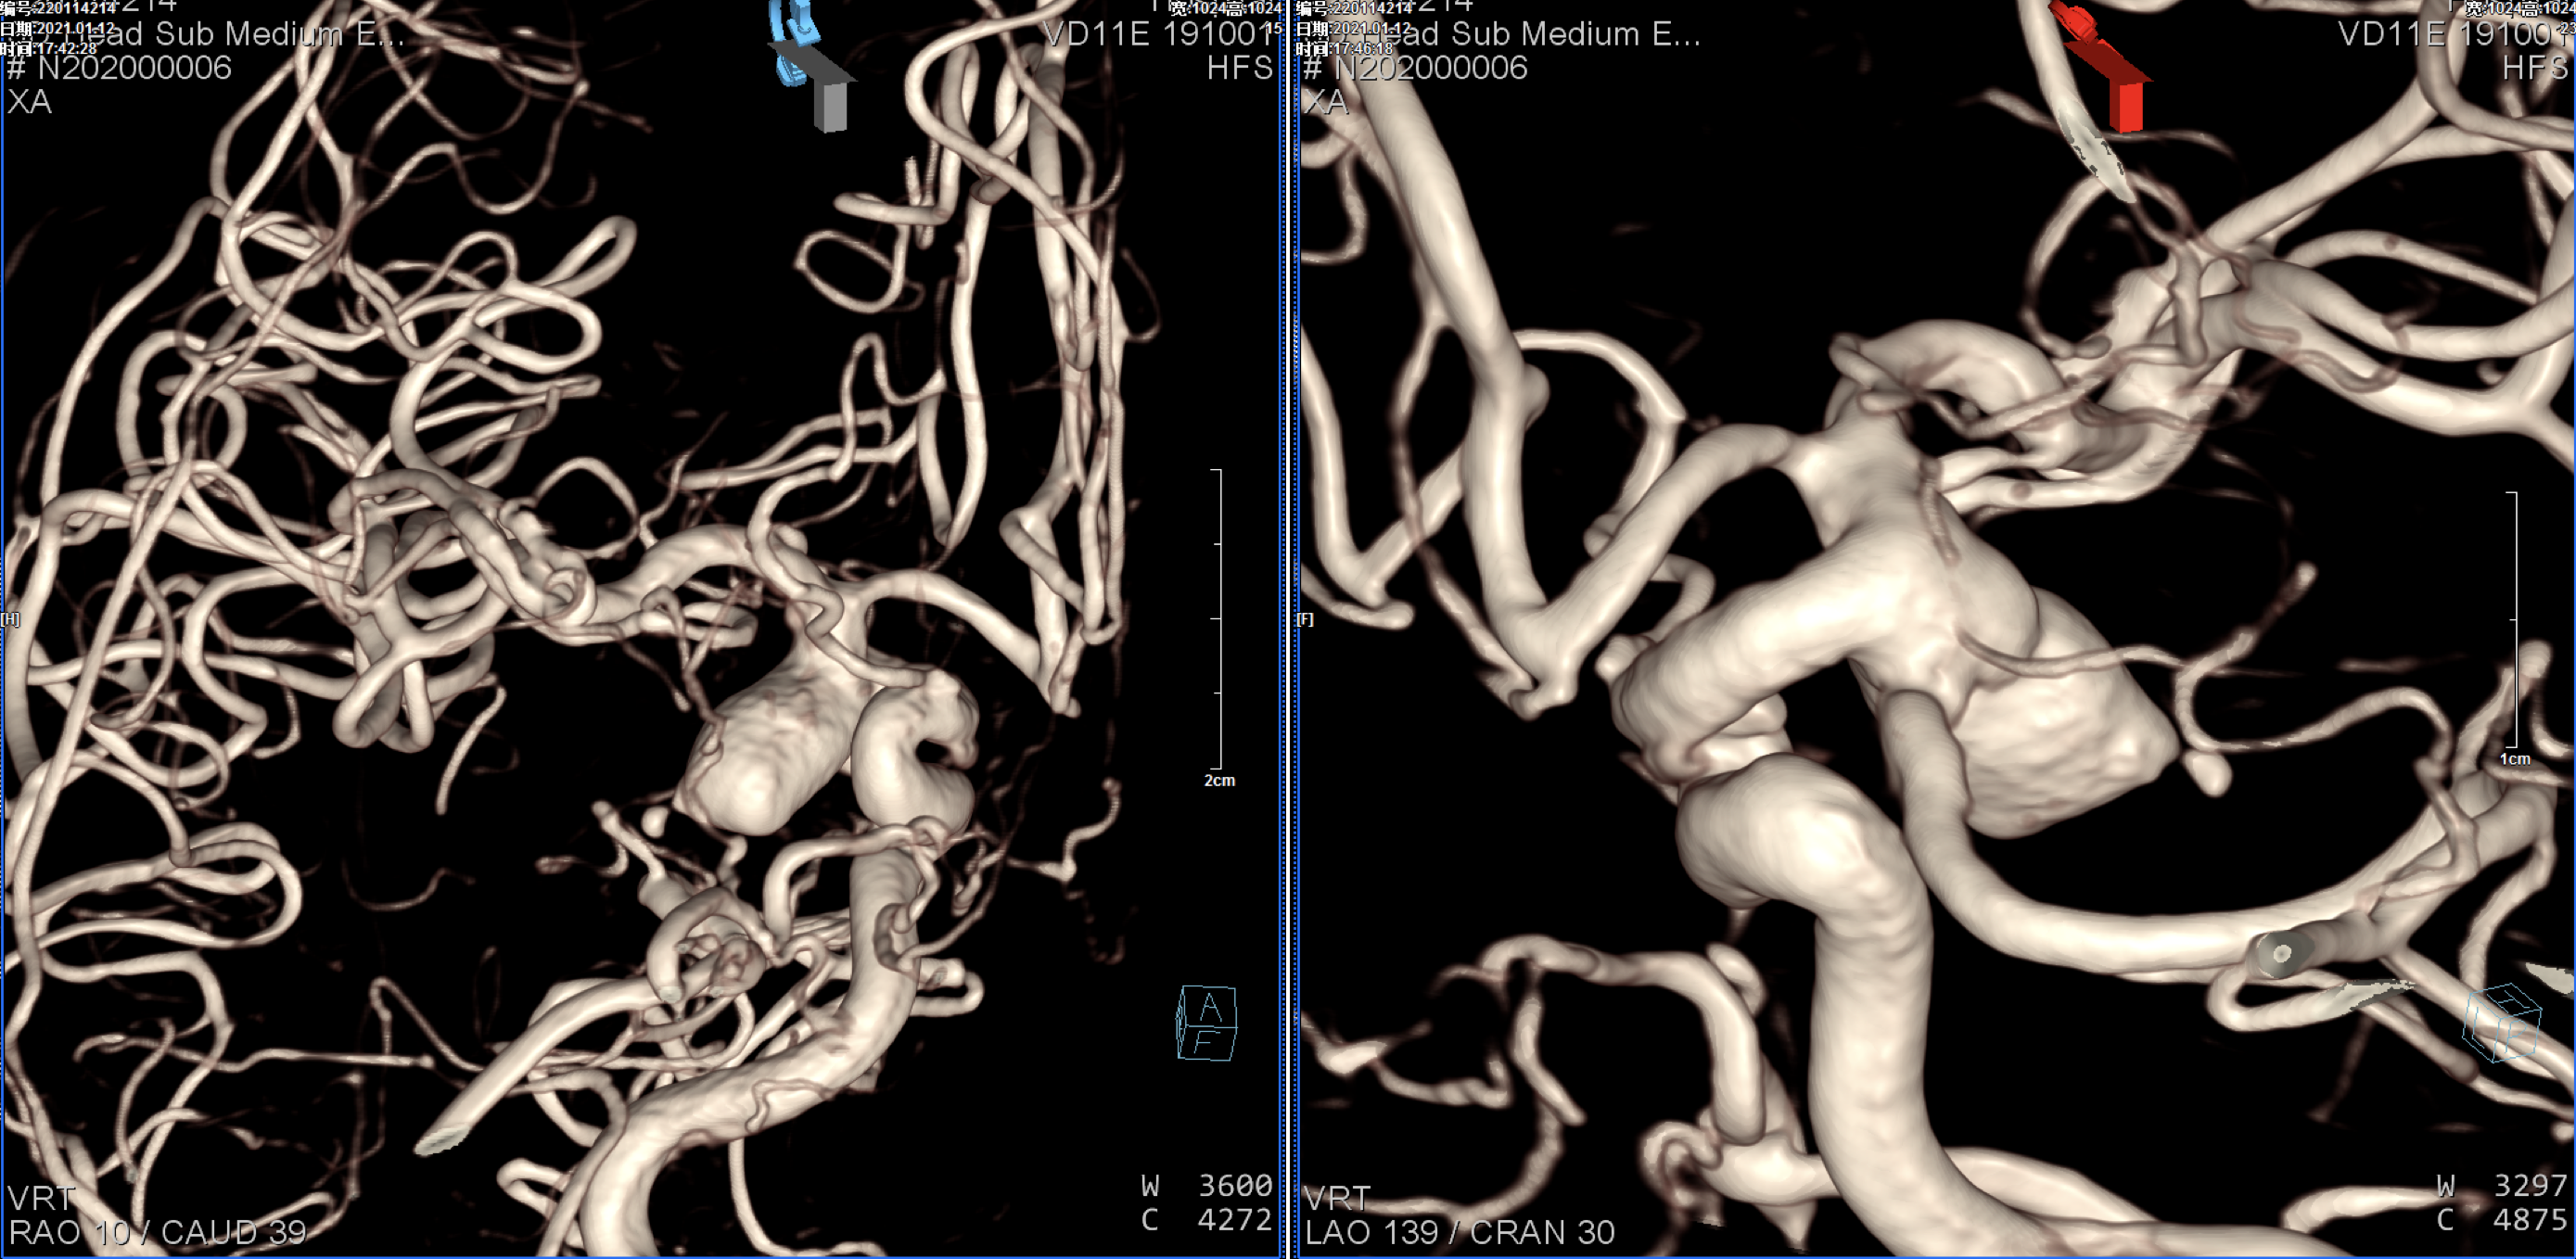

右侧颈内动脉正侧位造影:后交通动脉瘤,后交通动脉发育粗大!

右颈内动脉三维重建:粗大的后交通动脉自近心端瘤颈发出!闭塞后交通动脉可能会出现临床症状,似乎可以通过支架的推“灯笼”保护,但瘤体较大,尽可能栓塞完全,故考虑瘤腔内双微导管分区填塞!